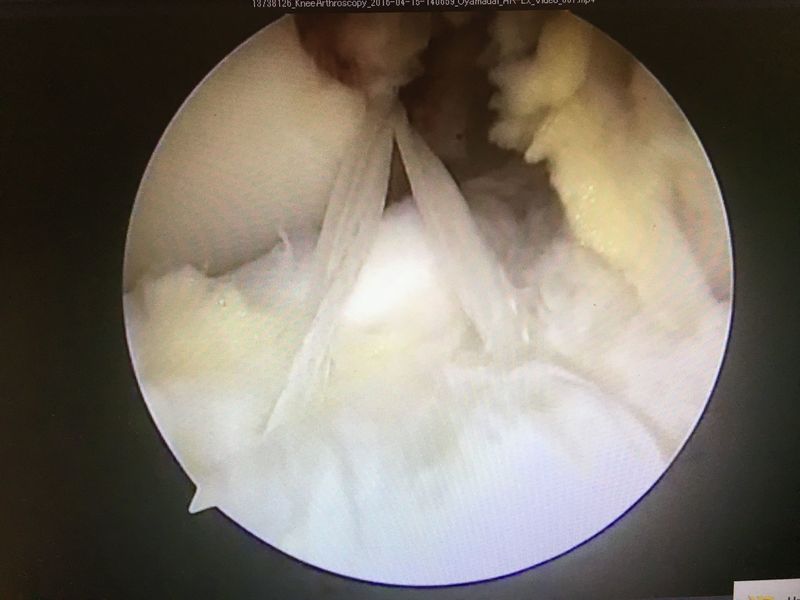

手術所見

|

ACLは緊張がなく機能していない |

外側半月板は問題なし |

内側半月板は問題なし |

ACL再建